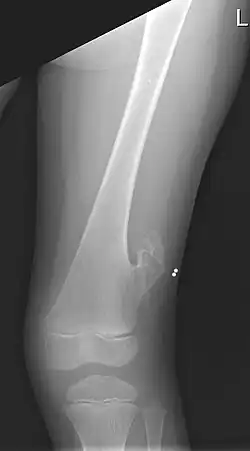

X-ray of the left femur of a 5-year-old boy with an exostosis at the lateral side, just above the knee.

An exostosis, also known as a osteochondroma, is a benign chondrogenic lesion derived from aberrant cartilage from the perichondral ring.[1] Exostoses can cause chronic pain ranging from mild to moderate, but rarely severe, depending on the shape, size, and location of the lesion, though most are asymptomatic and are found serendipitously on plain x-ray taken for other reasons. It is most commonly found in pre-teens through early 20s adjacent to the physes of the distal femur and proximal tibia but can be found adjacent to other physes, most notably the distal phalanx of the finger, where it presents as a subungual mass. larger growths can occur on places like the ankles, knees, shoulders, elbows and hips. Very rarely are they on the skull. Though rare, malignant transformation can occur into a chondrosarcoma.

They normally form growing stalks angling away from the physis toward the mid shaft of a long bone.